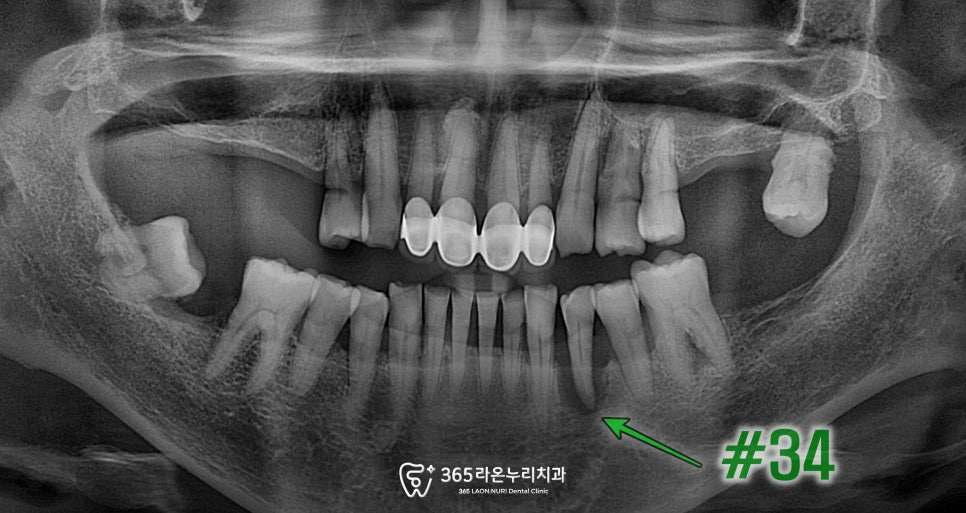

파노라마 엑스레이에서도

치조골이 많이 파괴된 양상이며

특히 표시 된 치아는

광범위한 골소실로

엑스레이에서도

뼈가 많이 녹아있는 모습을

확인할 수 있습니다.